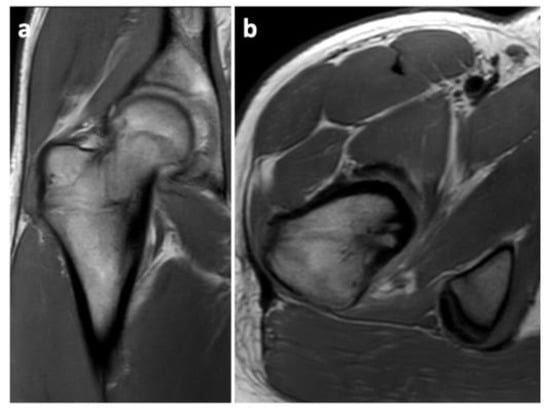

A histological examination proved that the lesion was indeed an osteoid osteoma. Further checkups have already been carried out at 3 months and at 6 months post-op. The patient has returned to his regular sports routine, and the musculature on his right lower extremity is gradually regenerating (Figure 8). At the 6-month post-op check-up, we took a long-format standing radiograph, which showed a slight valgus orientation of the proximal femurs; however, the stability of the right hip joint was not jeopardized even after our procedure (Figure 9). An MRI scan was also taken, and it proved the complete removal of the OO as well as the healing of the working canal (Figure 10). A further check-up is planned at one-year post-op.

Figure 10.

A 6-month post-op MRI scan showing no signs of relapse of the OO. (a) Frontal projection; (b) Transverse projection.